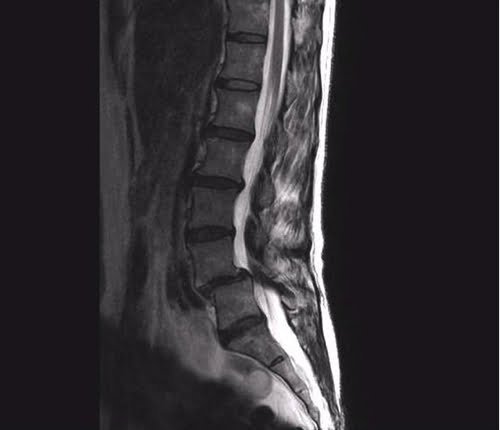

診断の出ている「すべり症」ですが画像検査ではこんな状況です。

けっこう大きなズレがある状態で初めて僕の院に来た際は

大きなズレのある「すべり症」でも痛みが消えないことはありません。